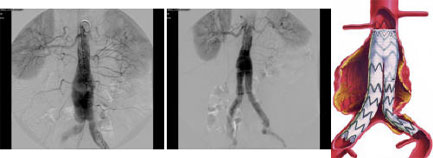

Beşinci hastamızda iskemik kalp hastalığı, yüksek tansiyon, kronik böbrek hastalığı (dialize bağımlı) ile birlikte bir abdominal aort anevrizması vardı. Genel anestezi alması imkansız olan hastaya epidural-lokal anestezi altında, sağ iliak arterde bulunan darlık tam kapatıldıktan sonra, tek taraflı (aorto unilateral-sol) endovasküler stent uygulanıp femoro-femoral cross bypass yapıldı.

Altıncı hastamız ağır akciğer tüberkülozu olup tedavi görmekteydi. Hastanın abdominal aort anevrizması 8 cm çapında olduğu için acil olarak ameliyat edilmesi gerekiyordu. Genel anestezi alması imkansız olan hastaya epidural-lokal anestezi altında, sağ iliak damarı tam tıkalı olduğu için tek taraflı (aorto unilateral-sol) endostent uygulandı. Femoro-femoral cross bypass gerek görülmedi.